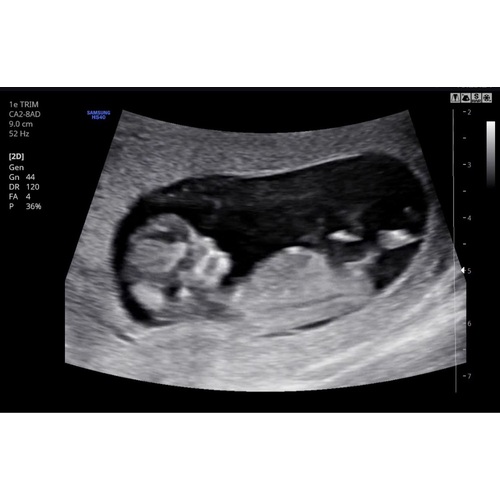

Wat denk je bij deze? 13+5

Vind dat een lastige daar kom ik eerlijk gezegd niet uit